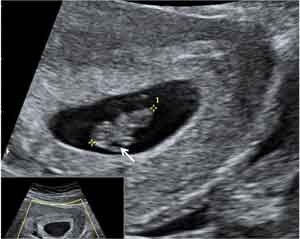

Ecografía en 2D de Embarazo de 7,5 semanas con embrión de 13 mm

Embrión de 13 milímetros, con un extremo más grueso (polo cefálico), donde aprecia una pequeña estructura quística (flecha), primer indicio visible por ecografía del cerebro en desarrollo.